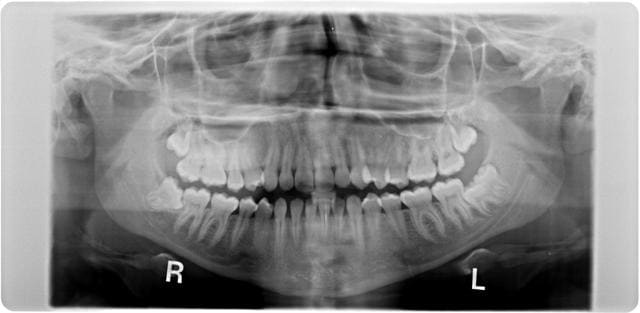

Des sagesses de toutes les formes vous attendent... Ca c etait ce matin...

Apres examen CBCT on laisse la 48 en place et si nouvel episode douloureux, coronectomie partielle.

Ps Sur la pano, 8 couronnes et une dent devitalisee(patiente de 75 ans). On a pas la meme secu.

Qui veut faire la 38?